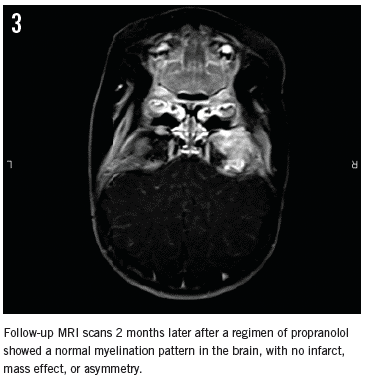

MRI results 2 months later showed a slight reduction in the bulk of the hemangioma (Figure 3). The exophthalmos mass effect related to the lesion on the right globe appeared to have improved after propranolol treatment. Nevertheless, since the MRI results did not show complete remission of the hemangioma, the regimen of propranolol 2 mg/kg/day was resumed. A follow-up MRI scan was to be done in 8 to 12 months.